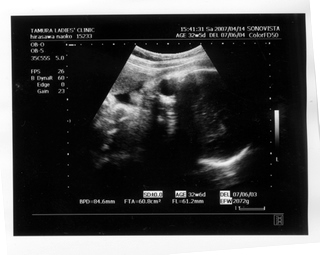

× [PR]上記の広告は3ヶ月以上新規記事投稿のないブログに表示されています。新しい記事を書く事で広告が消えます。 9ヶ月(32週と5日) 体重:2072g BPD(頭を上から見た耳から耳の幅のような感じ):84.6㎜ FTA(お腹の断面):60.8平方㎝ FL(大腿骨長 太ももの骨の長さ):61.2㎜ 9ヶ月(35週と2日) 体重:2583g BPD(頭を上から見た耳から耳の幅のような感じ):90.2㎜ FTA(お腹の断面):72.8平方㎝ FL(大腿骨長 太ももの骨の長さ):64.8㎜ 久しぶりの記事アップです ![]() なんだかあっという間にGW終わってしましましたね~ ![]() きのうは雨のせいでだらけてしまって、記事書く予定ができませんでした ![]() ダンナっちには『雨降って ナオコ 動かず』といわれています・・・ ![]() さてさて、5月2日(35週と2日)の内診では、 子宮口が1センチ開いてきてることが発覚 先生に「もう少し入れておいてよ 張ったら休まなきゃダメ」と言われ、 薬 まで出されました。子宮の筋緊張状態をやわらげて、早産を防止 するんだそうです。 「慣れるまでは心臓がドキドキしたり、 手が震えたりしますけど、大丈夫ですから」 と先生から説明を受けて、家で飲んでみると、 ほんとにドキドキ して、手もピクピク してきて、なんかラリった妊婦状態で不思議でした。 今週に入って、だいぶ慣れたようでそんなにラリっては いないけど、飲んでから1時間くらいは運転を控えています ![]() ベイビー自体は2500gをすでに超えて、動きも活発で元気にしています ![]() 1センチ開いてもなかなか進まないこともあるし、どうなるかはわかりません ![]() でも、ベイビーがお腹から出てきて自分で呼吸をするために、 必要な肺のサーファクタント(界面活性物質)の分泌は、妊娠33~36週ころから になります。 哺乳反射といって、ベイビーがおっぱいを飲むための反射的に吸い付く能力は 32~34週で完成するそうです。 網膜の血管が完成するのは35週前後だそうです。 つまり、わたしは今週臨月(36週)に入りましたが、 やっぱり正期産である37週からの出産が望ましいみたいです ![]() ![]() 医療も発達してきてるし、 ほぼ完成しているので生きられないことはぜんぜん無いんですけど、 十分に成長して「時」が満ちて生まれるのが一番みたいですね~ ![]() 「はやく会いたいけど、あと3週間くらいお腹の中にいてね~」 とベイビーに言っています ![]() 薬をもらってから、「張り」を意識するようになったんですけど、 けっこう張るんですよね~ 張るとなんとも動きづらい ![]() パンパンで重みのある厚手のゴムボール を持って歩くような・・・そして、 膀胱圧迫![]() ![]() ![]() トイレ行くにも駆け込む動作がつらい 歩けない![]() 、走れない![]() ![]() 悲惨な結末 ![]() ![]() ![]() ![]() を迎えまいとして、キュッと閉める運動をせざるをえなくなります・・・ ![]() PR この記事にコメントする